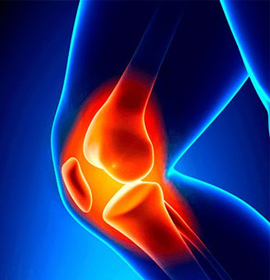

Una rotura del menisco es una de las lesiones de rodilla más comunes. Cualquier actividad que haga que tuerzas o gires la rodilla con fuerza, especialmente al poner todo tu peso sobre ella, puede llevar a que ocurra una rotura del menisco.

El síndrome de dolor patelofemoral es un término que se usa para describir el dolor en la parte delantera de la rodilla y alrededor de la rótula o hueso de la rodilla. El dolor y la rigidez que provoca puede hacer difícil subir escaleras, arrodillarse y realizar otras actividades cotidianas.

Cuando el cartílago se rompe y se desgasta, los huesos se rozan. Esto a menudo provoca dolor, hinchazón y rigidez de OA. A medida que la OA empeora, se pueden formar espolones óseos o hueso adicional alrededor de la articulación.